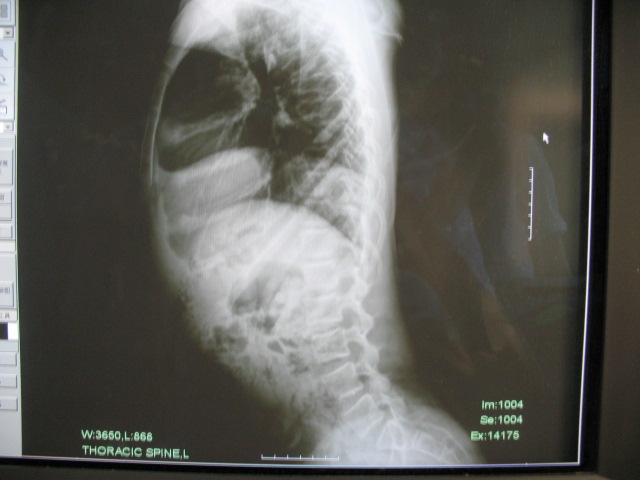

标题: PED0296:男,14岁,身材矮小,全身多处多次骨折 [打印本页]

标题: PED0296:男,14岁,身材矮小,全身多处多次骨折

骨干细而骨端膨大,多发性骨折,临床上可有典型蓝色巩膜、进行性耳聋、脆骨/三联症

成骨不全伴左髋关节脱位。成骨不全是侏儒的病因之一。[url][/url]http://www.radida.com/radinet/read.php?tid=27242

支持成骨不全,细长型

考虑:成骨不全伴左髋关节脱位。